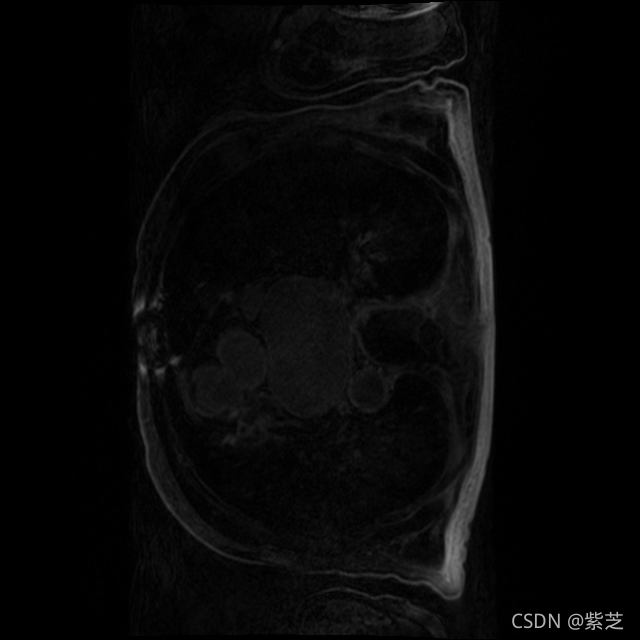

后来经过查询以及对三个通道的图像对比,怀疑第一维度上面的信息可能表示 患者接受扫描的期相,1 表示平扫,只有一期;2 表示增强,有动脉期和静脉期;3 表示造影,有动脉期、静脉期和平衡期。